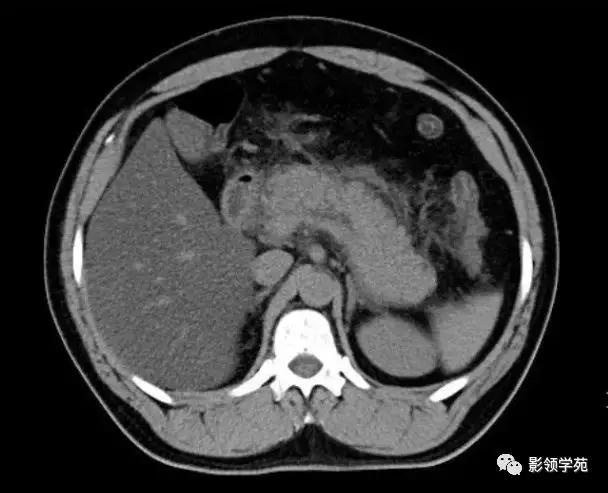

急性水肿型胰腺炎:CT平扫,胰腺明显肿胀,密度尚均匀,周围见条片渗出。